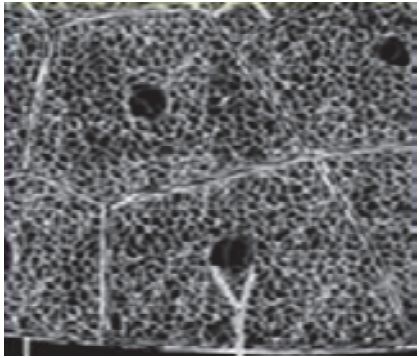

(四)细网格征、铺路石征

在磨玻璃病灶内部常可见细网格状阴影,类似铺路石状,称为细网格征或铺路石征(图 2-4) 。

提示病理改变为小叶间隔及小叶内间隔增厚,反映间质性病变,也有的学者解析为血管网增多,符合肺部病毒感染病理特性。

图 2-4 细网格征或铺路石征 (共4张)